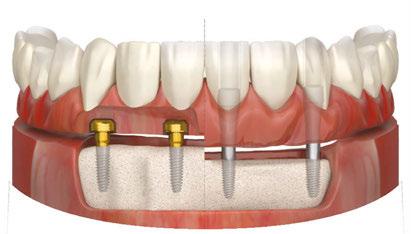

ZestMasters attendees now have the opportunity to learn how to convert removable LOCATOR® overdenture patients into LOCATOR FIXED™ patients simply by changing the inserts and housings, and modifying the prosthesis. This allows for seamless and affordable conversions and staged treatment planning or a FIXED full-arch treatment from the get-go. Learn more about LOCATOR FIXED at bit.ly/implantpractice_FIXED.

“The beauty of LOCATOR FIXED is that it uses the same abutments and workflow as the original LOCATOR to become a FIXED, full-arch solution that is removable by the clinician but not the patient,” said Dr. Scherer. “This is an affordable, simple, and less invasive way to deliver a FIXED full-arch option to an edentulous population that wants their smiles and confidence restored.”